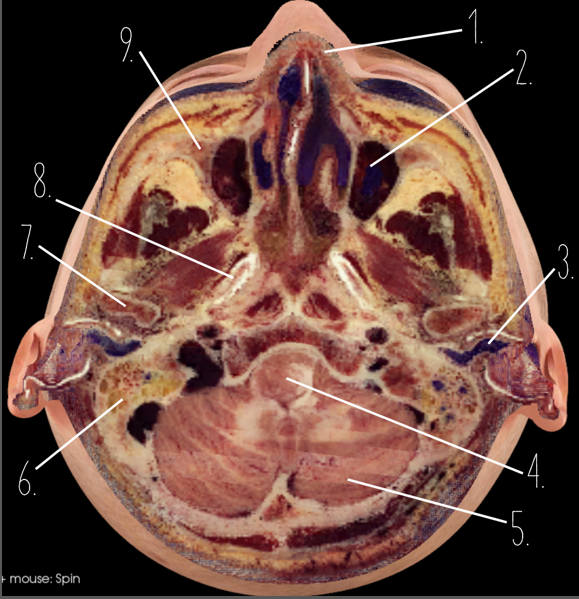

1?

Nasal Bone

2?

Maxillary Sinus

3?

External Acoustic Meatus

4?

Pons

5?

Cerebellum

6?

Mastoid Air Cells

7?

Mandibular Condyles

8?

Sphenoid Bone

9?

Maxillary Bone